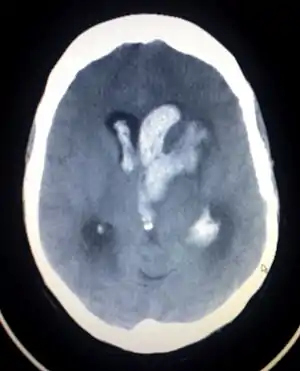

| سیتیاسکن از مغز دچار خونریزی داخلی | |

خونریزی میتواند حاد یا مزمن(مانند خونریزی سابآراکنوئید) باشد. تشخیص قطعی اغلب با سیتیاسکن یا MRI ممکن میگردد و در صورت تأیید تشخیص، درمان فوری (در جهت کاهش فشار داخلمغزی، قطع خونریزی و رفع ادم مغزی) ضروری است.